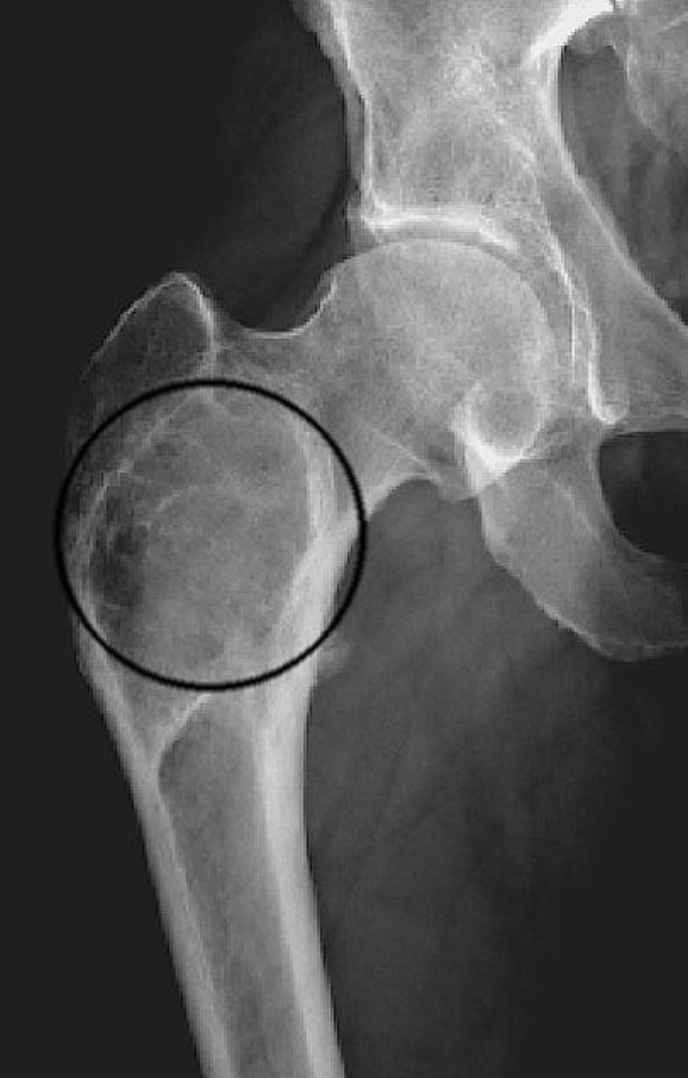

X-ray shows a soap bubble osteolysis and Shepherd’s crook deformity - what disease is it likely to be?

Fibrous dysplasia

Shepherd’s crook deformity: coxa varus angulation of the proximal femur, classically seen in femoral involvement